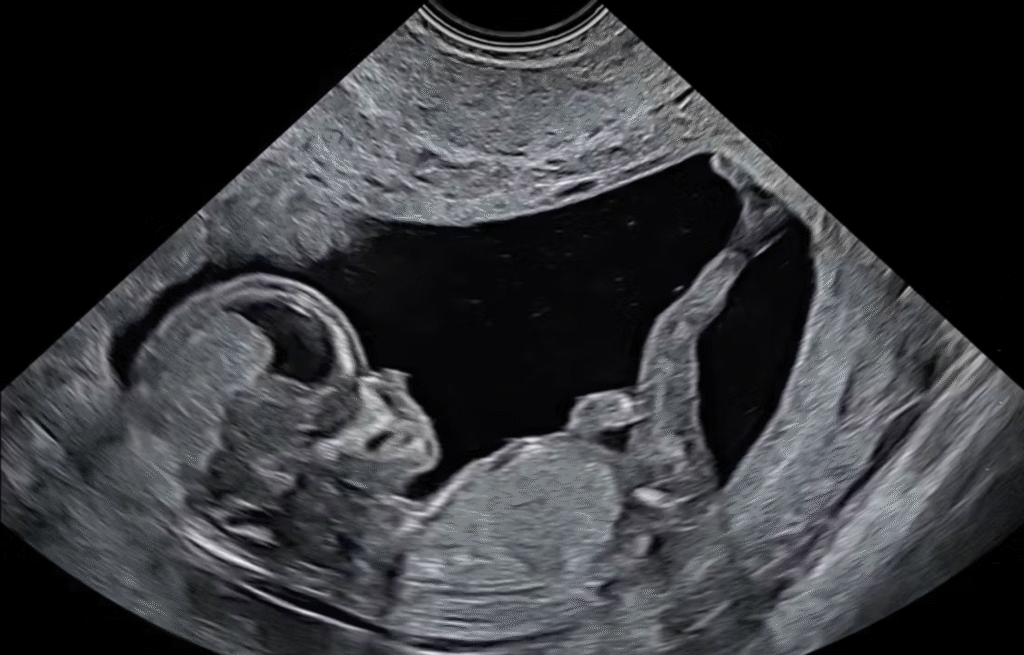

Investigation 4: Third Trimester – In this Investigation, students will learn about the technology that permits health professionals and parents to actually visualize the developing embryo and fetus. You will also examine the properties and important functions of amniotic fluid.